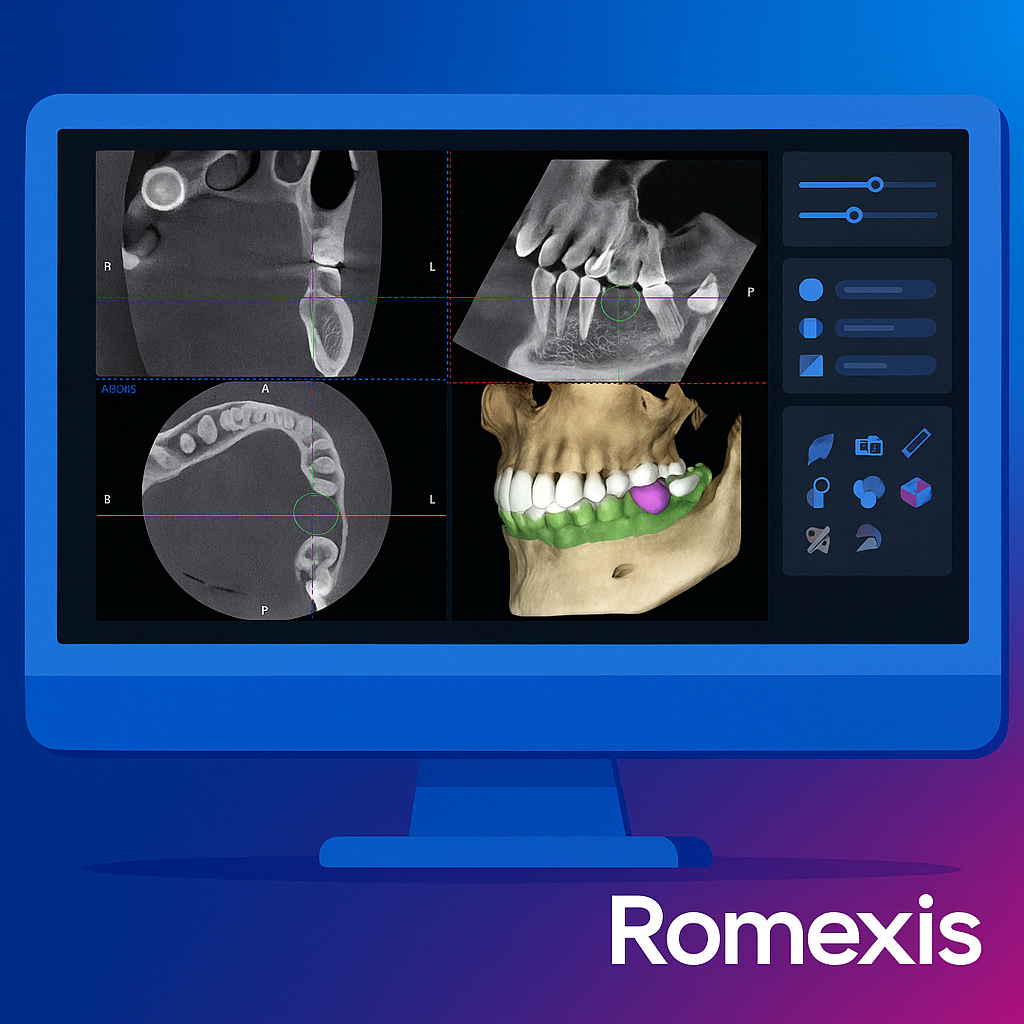

Виконуємо всі види рентгенологічних досліджень для стоматології та ЛОР

Призначається для діагностики стану всіх зубів, кісткової тканини верхньої та нижньої щелеп.

Записатися Детальніше